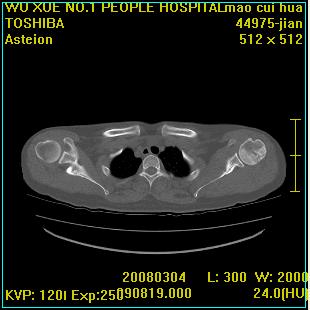

标题: CT12025:男,50岁,左肩活动受限半年。 [打印本页]

标题: CT12025:男,50岁,左肩活动受限半年。

肩关节骨质破坏呈小囊状,其周软组织轻度肿胀,余未见异常。

考虑:肩袖损伤。建议mri。

左侧肱骨头密度不均匀,高低混杂,周围软组织略肿胀,考虑结核性病变。

左侧肱骨头密度不均匀,高低混杂,髓腔密度稍高,周围软组织略肿胀,肌间隙模糊,考虑慢性骨髓炎可能。密切结合临床!